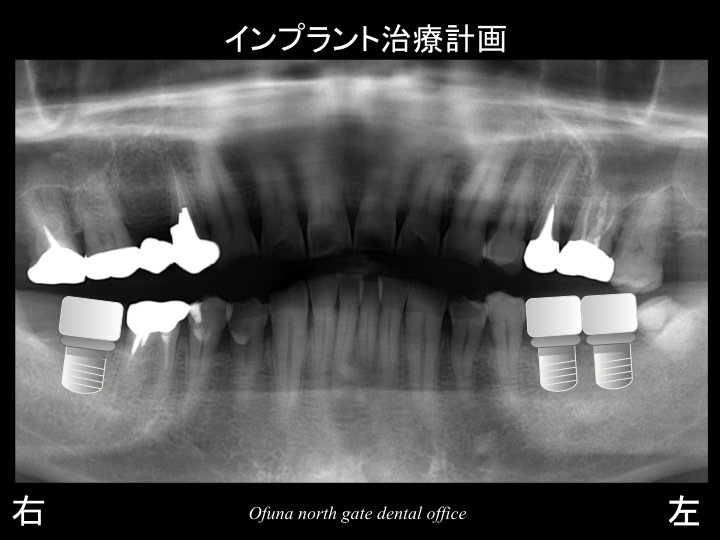

以下がインプラントの治療計画です。

以下は、インプラント治療後です。